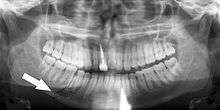

Panoramic radiographs have the capability to demonstrate a portion of the neck and display atheromas (calcifications in the carotid artery) which are an indication of both local and generalized (systemic) atherosclerosis. Atherosclerosis of the coronary arteries leading to myocardial infarction (heart attack), and atherosclerosis of the carotid artery leading to stroke are the number one and number three most common causes of death in the United States.[5]

There is interest to look at panoramic radiographs as a screening tool, however further data is needed with regards if it is able to make a meaningful difference in outcomes.[6]

Epidemiology: General Public and High Risk Groups

Additional research projects have further determined the prevalence rate of these atheromas in the general population (3-5%)[7] and among high-risk groups (over 25% in: recent stroke victims,[8] individuals with obstructive sleep apnea syndrome,[9][10] postmenopausal women,[11] type 2 diabetics,[12][13] individuals with dilated cardiomyopathy,[14] and among individuals who have received radiotherapy directed at the neck,[15][16]). These findings have been corroborated by other several other researchers.[17][18][19][20]